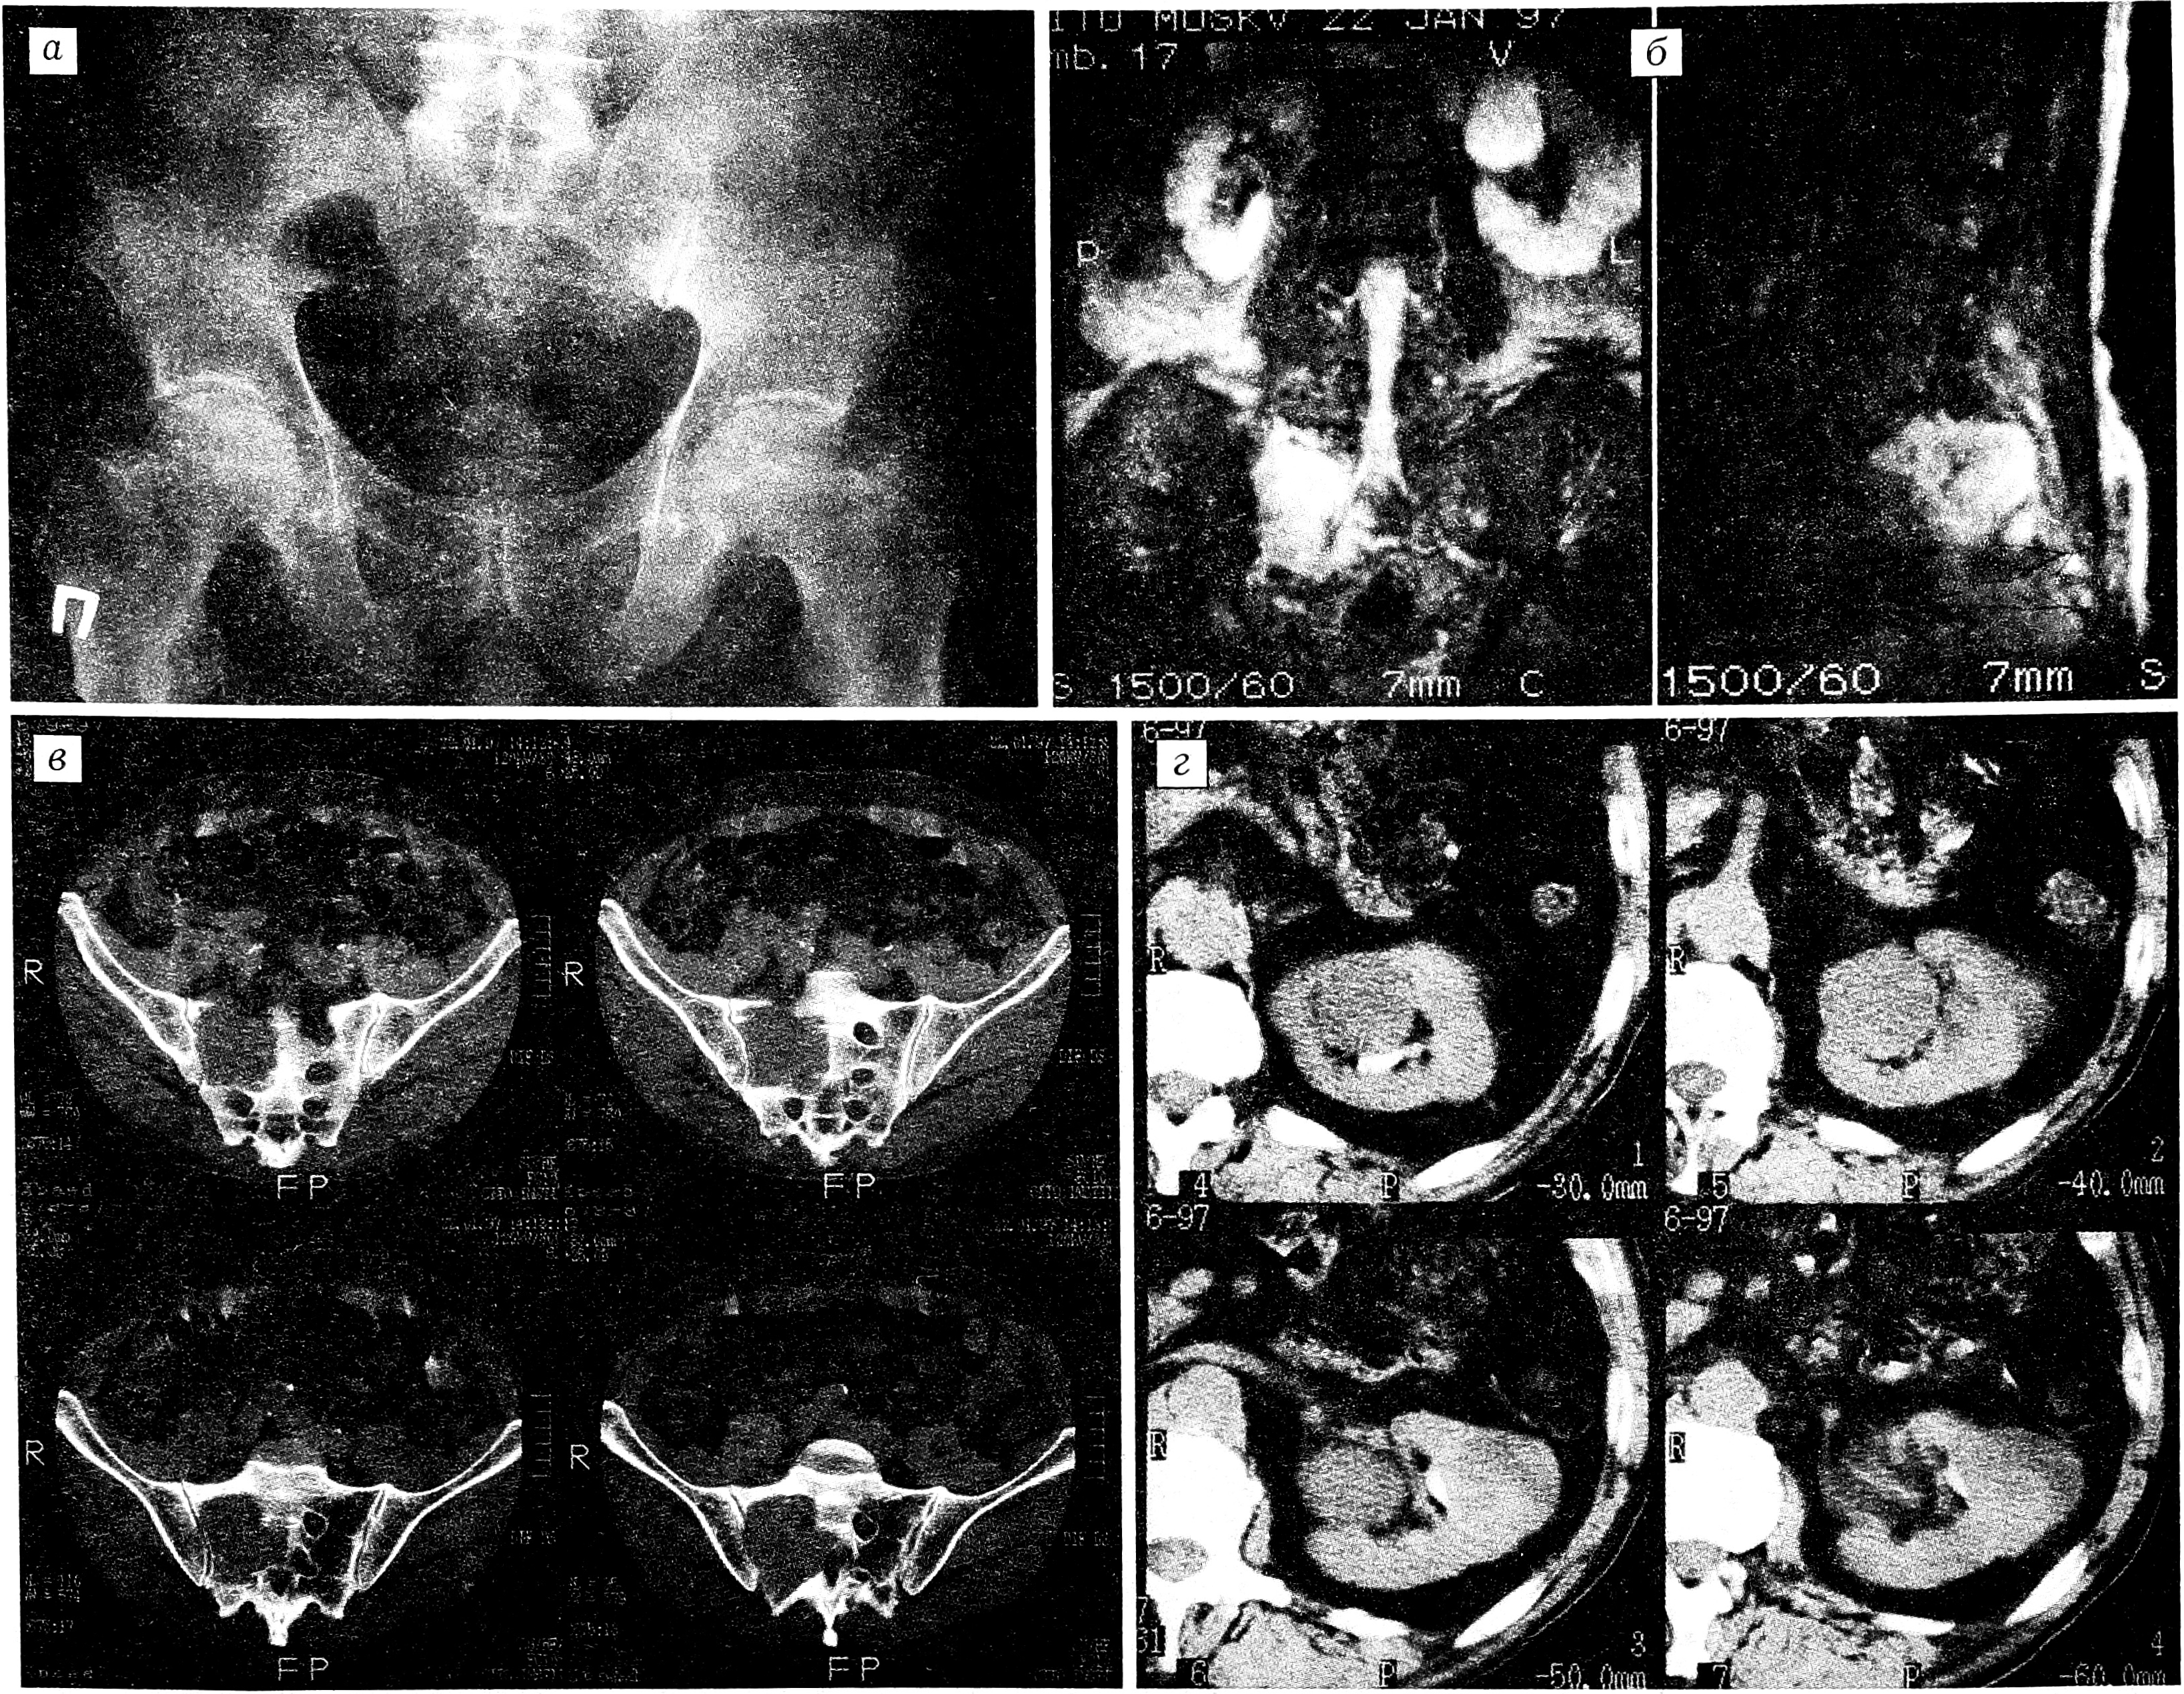

Рис. 3. Больной М., 43 лет. Диагноз: злокачественная остеобластокластома крестца.

a — обзорная рентгенограмма в прямой проекции; б — КТ: остеолитический очаг деструкции крестца и его боковых масс с внутритазовым компонентом, отдельные участки обызвествления и костеобразования в толще опухоли.

Рис. 4. Больной М., 34 лет. Диагноз: неврилеммома S3-S5, рецидив, озлокачествление.

a — аксиальная КТ: остеолитический очаг деструкции S3-S5, экстравертебральный компонент опухоли, грубые обызвествления и костеобразование; б — Т1 взвешенные МРТ в сагиттальной проекции: изоинтенсивный гетерогенный сигнал от опухоли в форме «песочных часов», гипоинтенсивный сигнал от капсулы; в — Т2 взвешенные МРТ в сагиттальной проекции: гиперинтенсивный сигнал от опухоли.